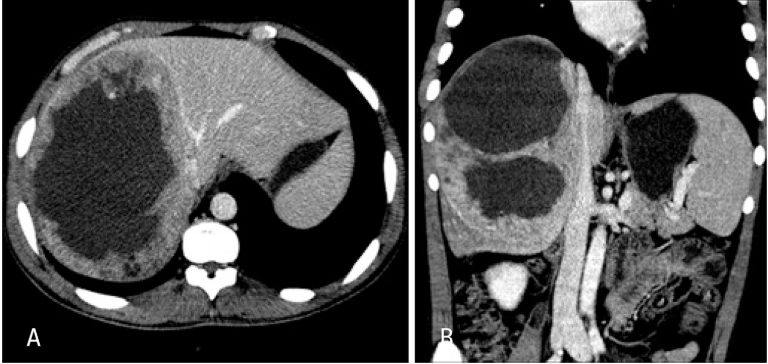

caso de tumor neuroendócrino metastático de intestino delgado com quadro característico de síndrome carcinoide. Fonte: https://doi.org/10.1590/0102-672020190001e1492